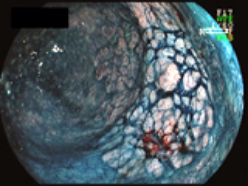

早期大腸癌に対するESD

1.直腸に認められたφ7cmの病変(左:通常観察、右:色素内視鏡観察)